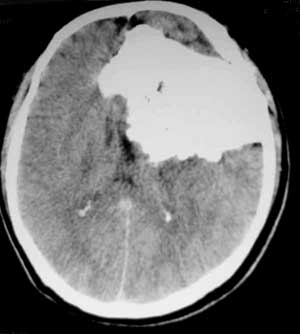

男性,60岁,反复癜痫40余年。

病理结果

:

骨软骨瘤